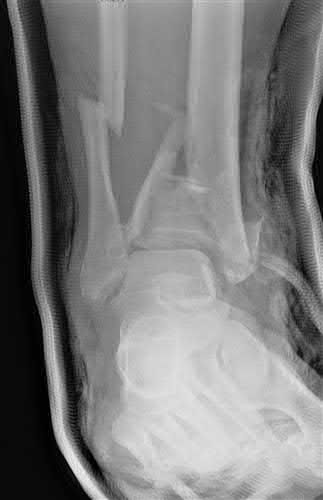

A 34-year-old male sustains the closed injury seen in Figure A as a result of a high-speed motor vehicle collision. What is the most appropriate next step in treatment?

The radiograph shows a comminuted pilon fracture, which is associated with high-energy trauma and significant soft tissue injury. The tested concept here is the importance of avoiding definitive reduction and fixation of this high-energy injury, which has been shown to be associated with an increased risk of wound complications and deep infections (as compared to staged treatment with usage of a spanning external fixator).

Patterson et al. reviewed 23 consecutive patients with comminuted distal tibia fractures. They showed 0% infections or wound-healing problems in their patient population treated with a two-staged protocol. Their protocol involved fibula fixation with an intramedullary implant and application of a medial external fixator to to regain length and restore anatomic alignment. Reevaluation of the limb occurred ten to fourteen days later for definitive fixation.

Sirkin et al. retrospectively reviewed 40 closed and 17 open pilon fractures (AO types 43A-C) that were treated with staged surgical management (avg. time from ext. fix. to formal reconstruction was 14 days (range 4 to 31) They reported 17% post-operative wound complication in the closed group and 11% post-operative wound complication in the open group (Gustilo Type I-III). They suggest the technique was successful in both closed and open pilon fractures.